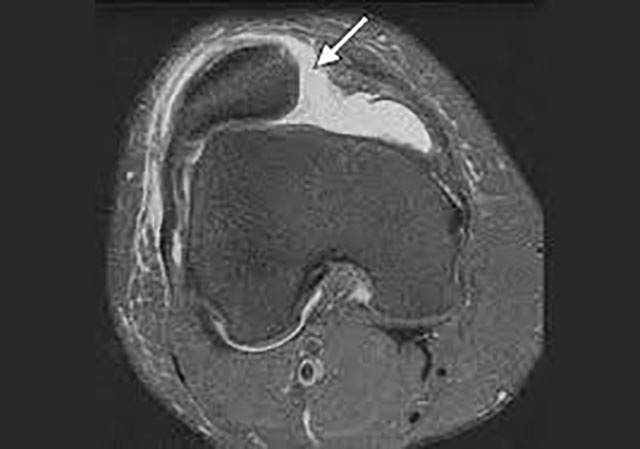

Надколенник смещен

Надколенник смещен 116 фото